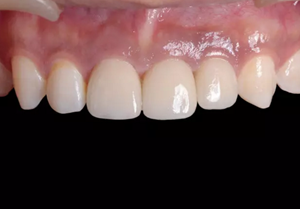

圖23 最終修復(fù)后即刻口內(nèi)像

圖25 最終修復(fù)后復(fù)查口內(nèi)像